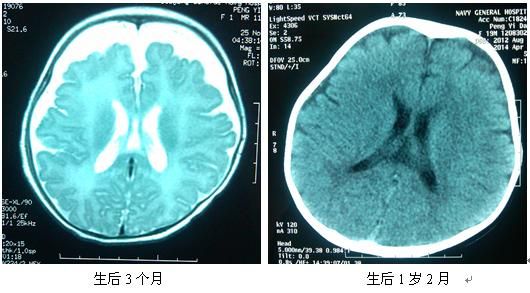

脑外示增宽是婴儿检查头颅CT或头颅核磁(MRI)片做出的诊断,有的诊断为脑外积水,甚至有的诊断为脑发育不良。有的受检查的孩子接受很多的治疗,包括注射药物、各种康复治疗。使孩子饱受痛苦,家长在精神受折磨和经济受损失。其实,婴儿头颅CT或头颅核磁(MRI)片显示脑外间隙增宽对于头颅大小正常的宝宝是正常现象。因为颅骨长得快,脑组织长得慢,在脑外显示间隙。下面有一位早产宝宝3个月时脑外间隙增宽,1岁2个月时脑外间隙增宽消失,智能发育正常的实例。

阳阳,女,29w剖宫产,母亲孕期有保胎史,余孕期检查未见异常,新生儿期患有高胆红素血症、新生儿贫血、新生儿肺炎等。眼底及听觉诱发电位无异常,3个月时头颅核磁共振(MRI)时脑外间隙增宽,。自纠正月龄1个月开始定期来诊,给予喂养、护理及运动、智能训练指导。未用如何药物或治疗仪器治疗。每次神经运动检查均未发现异常。6个月和17个月智测均为正常。1岁2个月时脑外间隙基本消失。

这个例子是早产儿在出生3个月时有脑外间隙增宽,出生1岁2个月时脑外间隙增宽基本消失。智力测查为正常。还有很多足月出生的宝宝也有脑外间隙增宽,我随诊观察了足月出生的宝宝50例有脑外间隙增宽的婴儿到2岁,他们停止了如何药物或仪器治疗,只给家庭早期教育的指导,2岁时智能运动发育完全正常。其中有的婴儿复查了头颅核磁共振,脑外间隙增宽消失。因此,正常儿或早产儿等高危儿脑外间隙增宽为正常发育过程,不需要治疗。